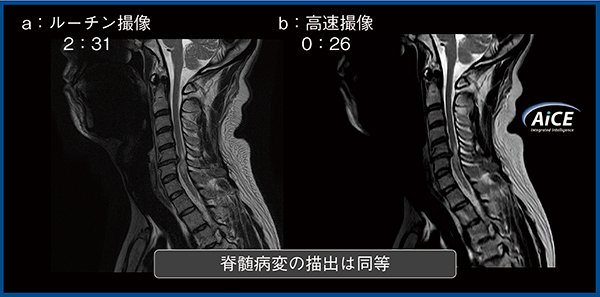

学習部位と異なる腰椎撮像の検証では,AiCE適用により3倍速撮像でもルーチン撮像と同等の画質を得ることができ,AiCEの汎用性が確認された。

また,6倍速の脊椎高速撮像とルーチン撮像の病変描出能の比較では,同一読影者内のkappa値は0.7以上であり,病変描出能は実質的に一致していると解釈できた(図2)。DLRの登場により,救急患者や安静保持が困難な患者向けに,病変描出能が保持された脊椎高速撮像が可能となったと考えられる。

図2 頸椎のルーチン撮像と高速撮像の比較